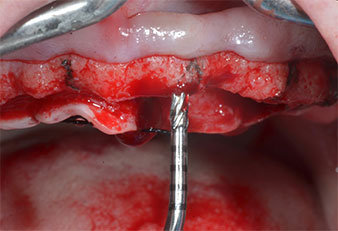

Инструменти I2A/I2P за Piezomed

Фиг. 4 Следващата стъпка е пилотно разширяване с накрайници I2A/I2P, които прилагат ротационно хоризонтално движение.